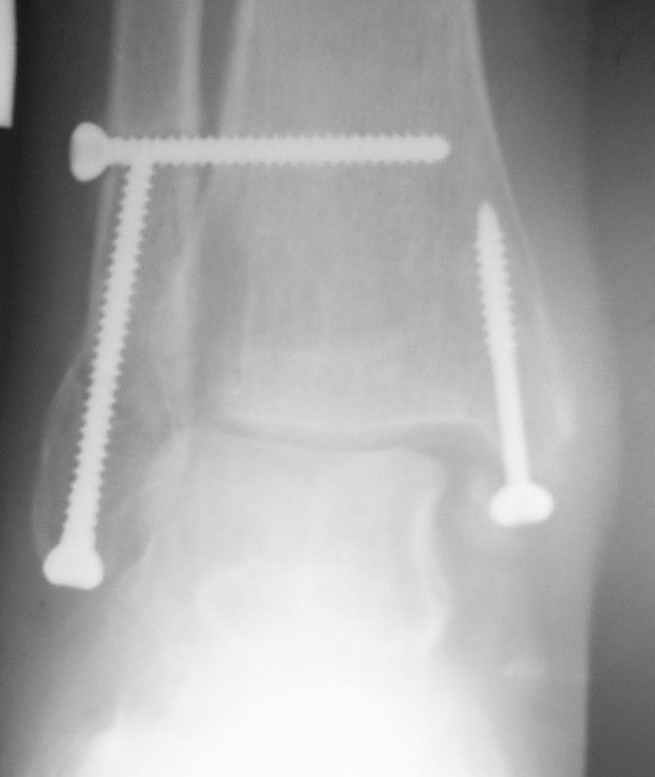

Ниже рентгенограммы

До операции 28 июля

Риторический вопрос - в каком руководстве рекомендован такой способ остеосинтеза наружной лодыжки?

Очевидно, такой результат операции был запрограммирован. При невосстановленной длине и практически нефиксированной малоберцовой кости (этот кортикальный винт - как карандаш в стакане), при неустраненном подвывихе, невправленной и тоже нефиксированной внутренней лодыжке нет стабильной вилки сустава. Если такую операцию сделать даже сразу, а не через 4 месяца, то результат ожидаем

тот же.

Вообще говоря, такое повреждение вполне успешно можно лечить без операции - если 6 недель подержать в гипсовом "сапожке" с хорошо устраненным подвывихом. Вероятное несращение внутренней лодыжки не обязательно компрометирует результат.

Ну а уж если выбран остеосинтез - нначать надо было с репозиции малоберцовой кости с точным восстановлением длины, с фиксацией треть-трубчатой пластиной по задней поверхности. Позиционный винт

избыточен - повреждение практически подсиндесмозное. А если бы

действительно было повреждение синдесмоза - в 4 месяца позиционный винт - не решение. Внутренню лодыжку такую - надо было бы спицами и проволочной петлей. Извините за эти банальности.